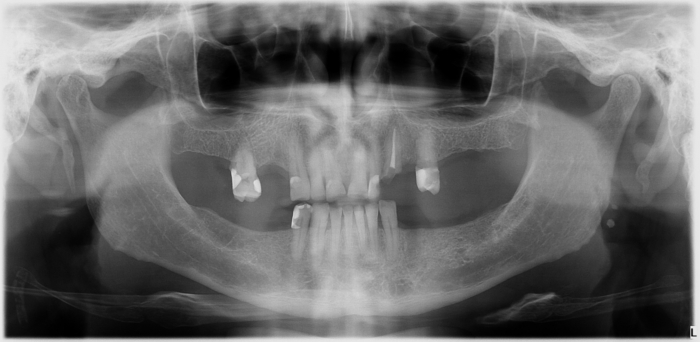

Rx Inicial